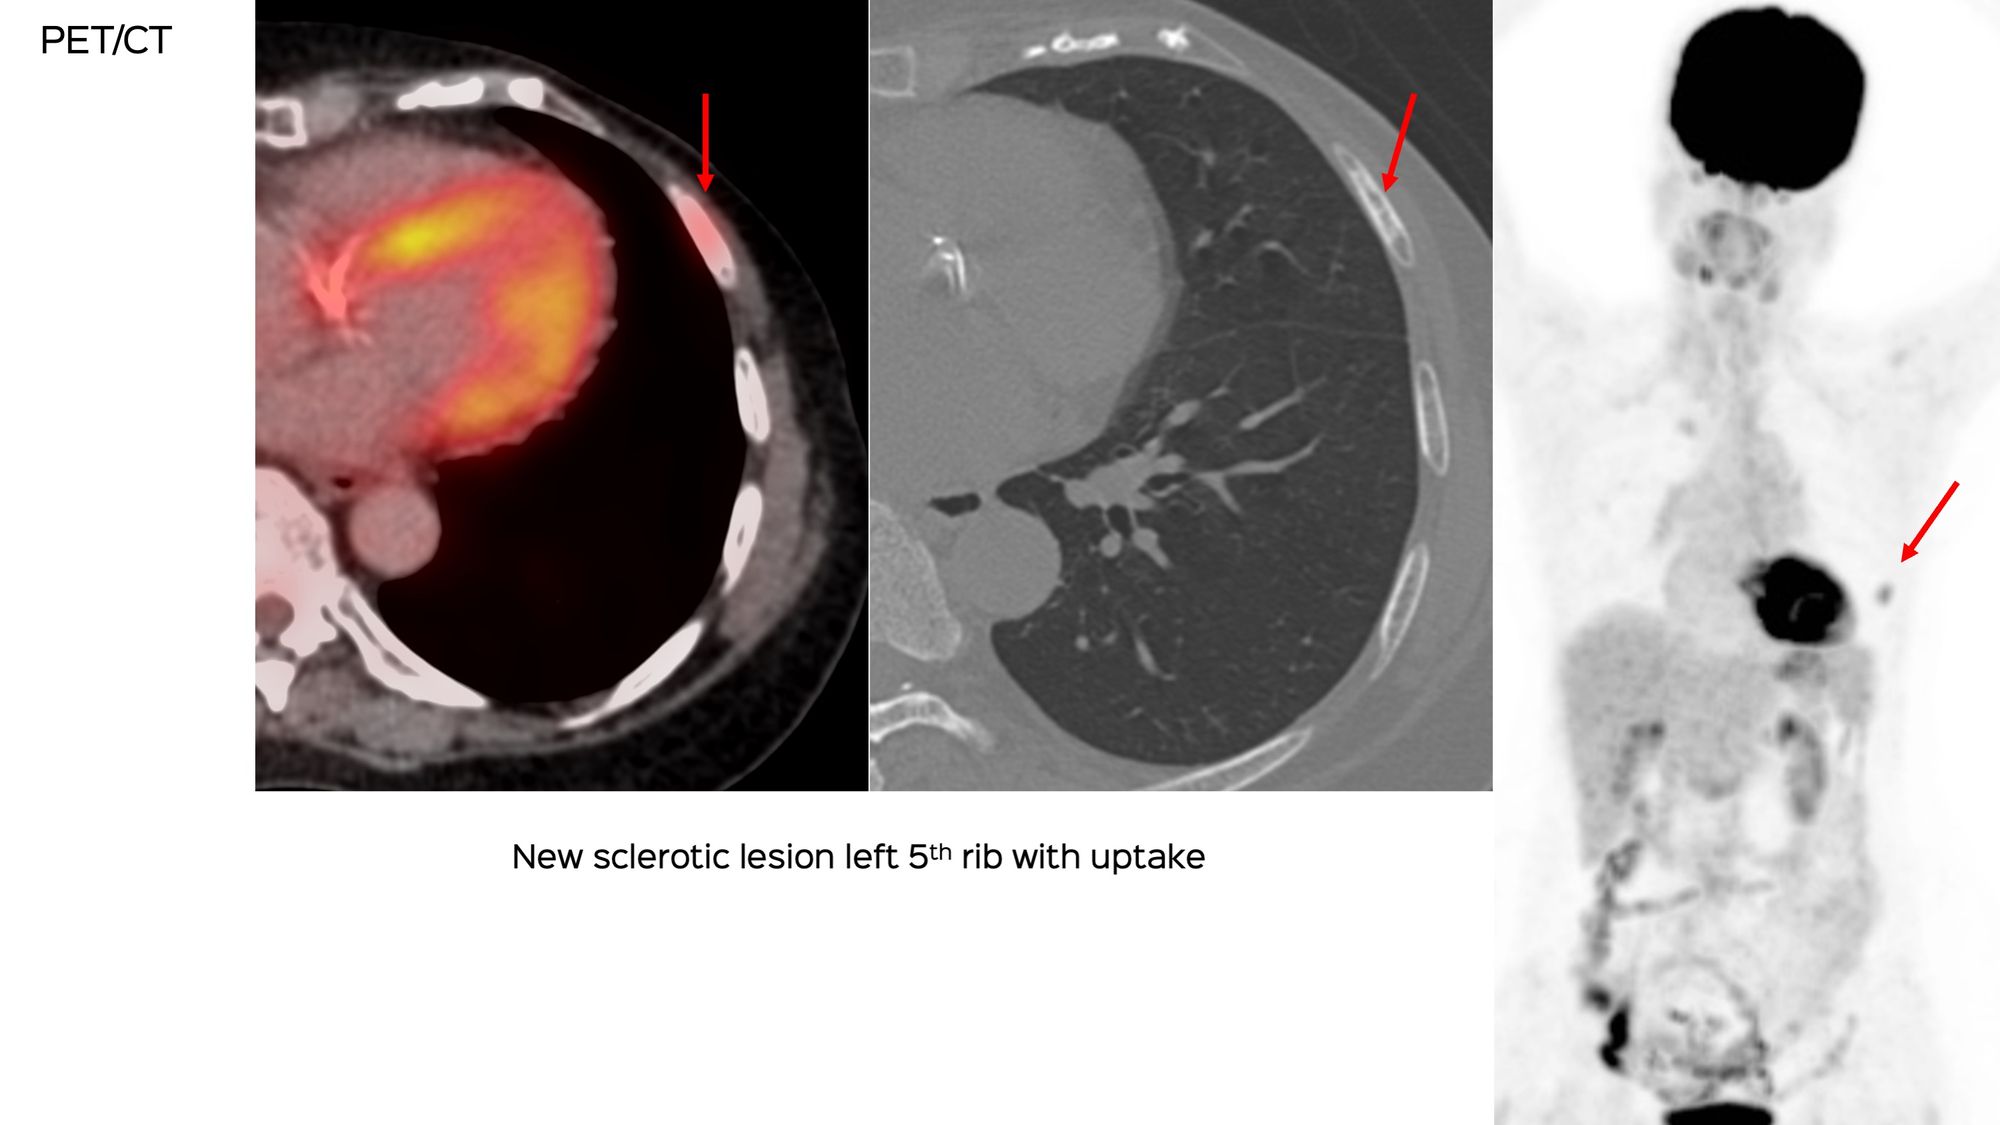

A 70-years old treated in the past for carcinoma breast was found to have a new, sclerotic left 5th rib lesion on PET, confirmed on MRI. She was refused a biopsy because of the risk of lung injury.